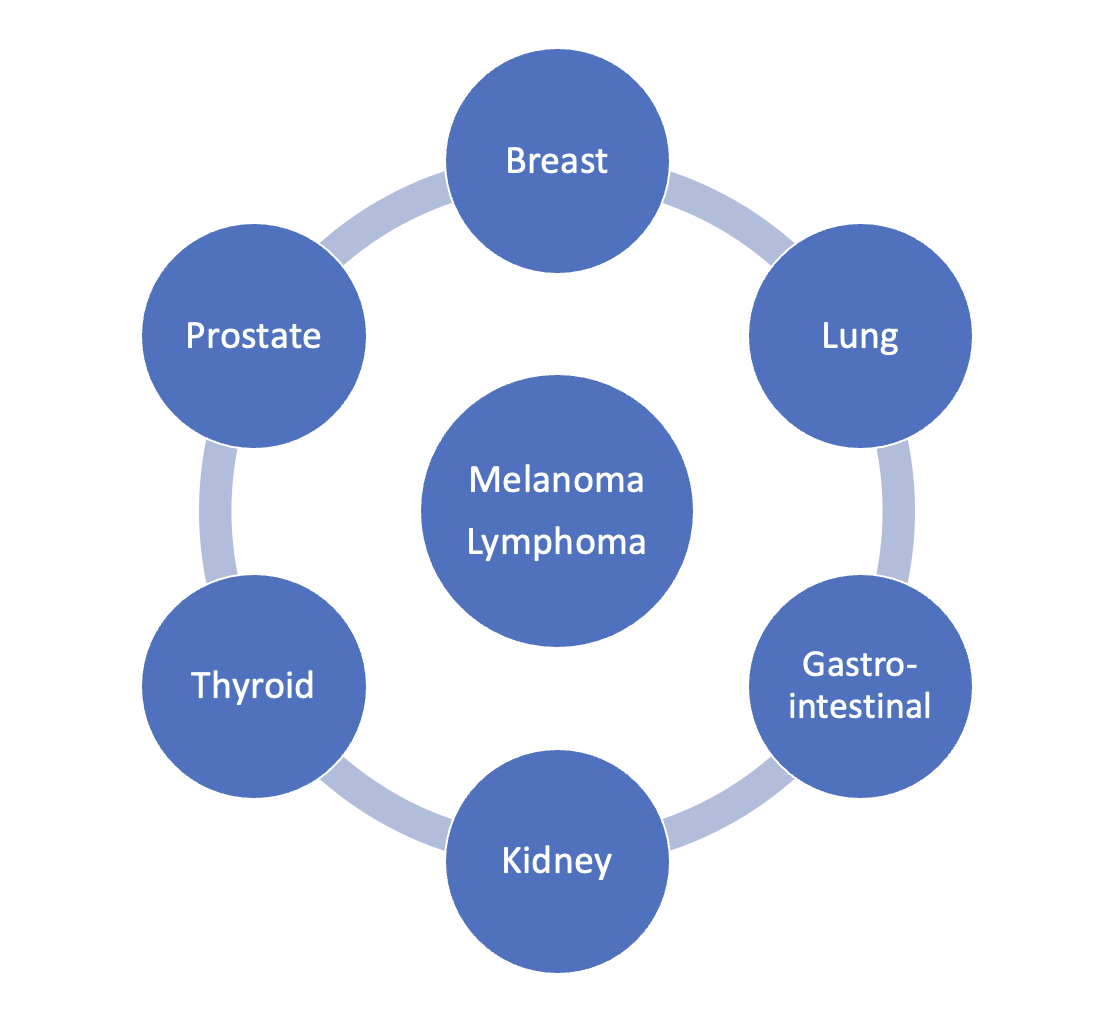

Cancers with bony metastasis (Hexagon)

80% PBL (Prostate, Breast, Lung)

20% Kidney, Thyroid & GI + Melanoma / Lymphoma